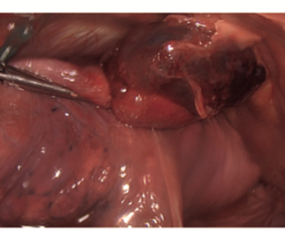

Julián Andrés Díaz Santamaría, Marco Tulio Gonzalez, Arnaldo Almendros Mello

|

|

|